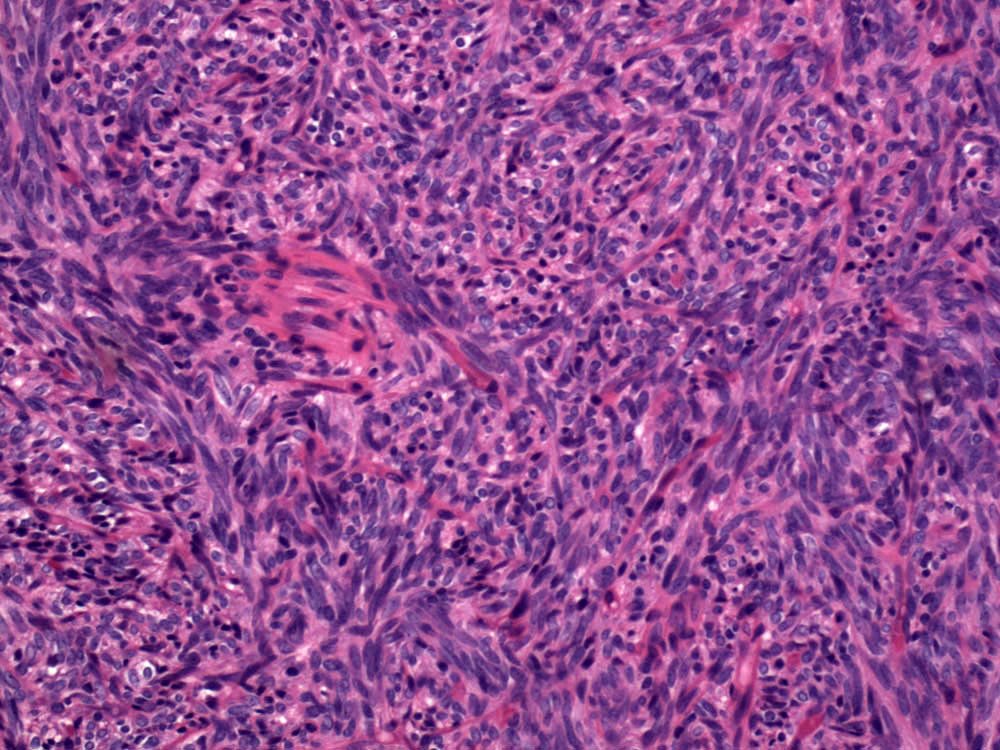

Case: ShoulderMass

Final Diagnosis: